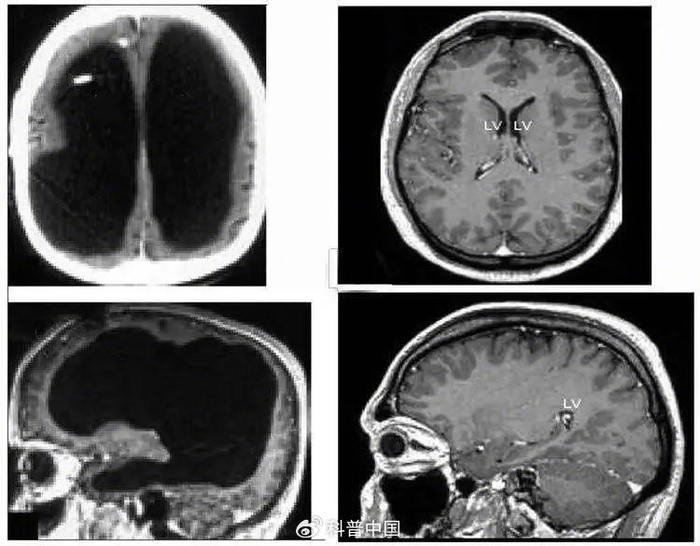

扫描的结果令所有人大吃一惊。他的大脑中央是一滩巨大的积水,脑子被挤压到了边缘薄薄一层。当然严格来说这也不是纯水,而是脑脊液。正常人脑子内有少量的脑脊液,不断产生又不断排出到循环系统里,保持总量稳定,但这位患者脑内的排水系统发生了障碍,进多出少,导致液体越积越多。

左边为这名法国男子的大脑,中间黑色部分都是脑脊液;右边为正常人的大脑